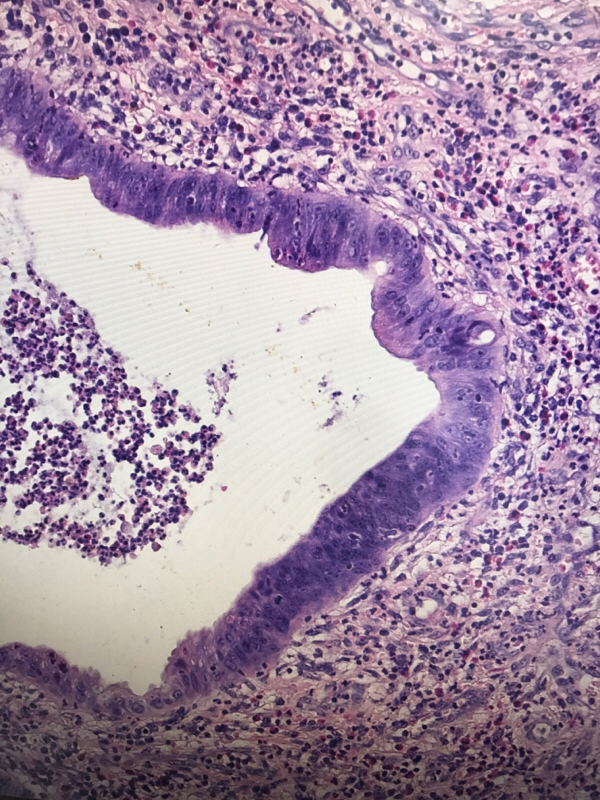

直肠息肉

性别

男

年龄

19

临床诊断

一般病史

血便4天

标本名称

大体所见

灰红结节一枚,大小1✖️0.6✖️0.6cm,切面灰红,质软

管状腺瘤,低级别还是高级别?

幼年性息肉,灶性低级别

考虑有高级别

幼年性息肉?

幼年性息肉